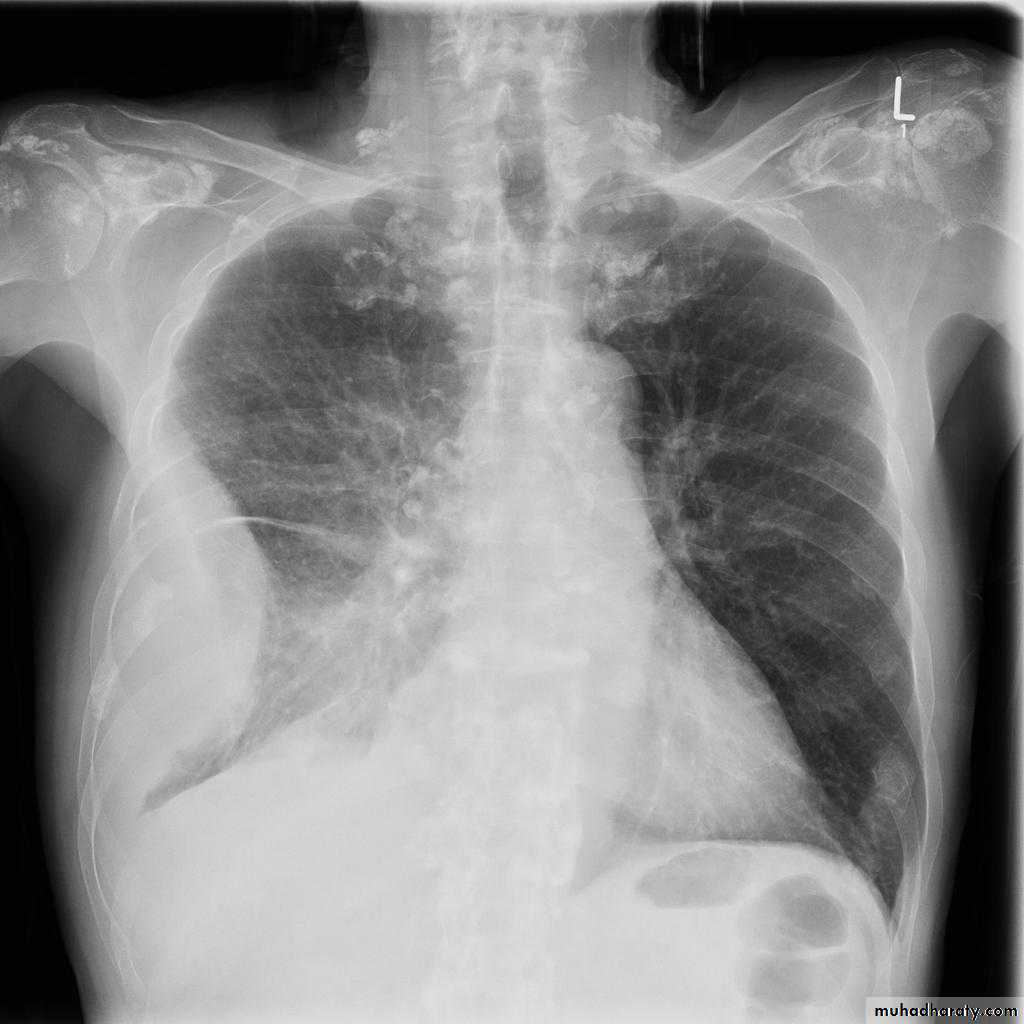

Pleural effusion

Pleural effusion tends to be used as a catch-all term denoting a collection of fluid within the pleural space. This can be further divided into exudates and transudates depending on the biochemical analysis of aspirated pleural fluid. Essentially it represents any pathological process which overwhelms the pleura's ability to reabsorb fluid.Radiographic appearances

Plain radiographChest radiographs are the most commonly used examination to assess for presence of a pleural effusion, however it should be noted that on a routine erect chest x-ray as much as 250-600 ml of fluid is required before it becomes evident 6. A lateral decubitus film is most sensitive, able to identify even a small amount of fluid. At the other extreme, supine films can mask large quantities of fluid.

CXR (erect)

Both PA and AP erect films are insensitive to small amounts of fluid. Features include:

blunting of the costophrenic angle

blunting of the cardiophrenic angle

fluid within the horizontal or oblique fissures

eventually a meniscus will be seen, on frontal films seen laterally and gently sloping medially (note: